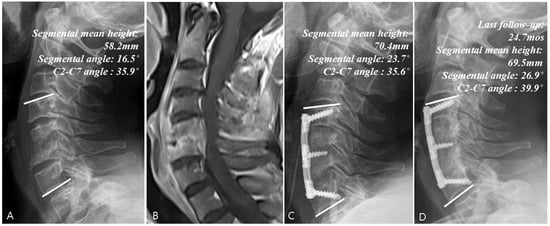

| Segmental angle (°) | |||||

| -First visit | −2.7 ± 3.1 | −2.4 ± 5.9 | −2.7 ± 4.7 | 1.000 * | (−1.2, 1.5) |

| -Last follow-up | −3.1 ± 3.8 | 2.7 ± 5.4 | −2.8 ± 4.6 | <0.001 * | (2.8, 9.2) |

| p-value a | 0.724 ^ | <0.001 ^ | 0.981 ^ | ||

| C2-C7 angle (°) | |||||

| -First visit | 8.4 ± 8.1 | 8.2 ± 7.8 | 9.4 ± 6.0 | 0.797 * | (−2.1, 2.5) |

| -Last follow-up | 8.1 ± 6.8 | 16.7 ± 8.4 | 9.1 ± 7.3 | 0.001 * | (3.2, 13.8) |

| p-value a | 0.859 ^ | <0.001 ^ | 0.744 ^ | ||

| Mean height change (%) | −19.3 ± 11.9 | 14.0 ± 15.8 | −7.8 ± 10.9 | <0.001 * | (18.5, 42.3) |

| Fusion achievement | 2/14 | 27/32 | 6/13 | <0.001 ‡ | (28.4%, 80.2%) |